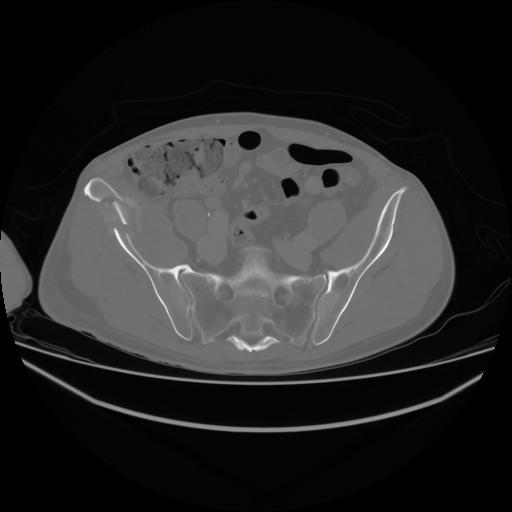

4 CUERPO,CE,Axial,3.0,CUERPO,,